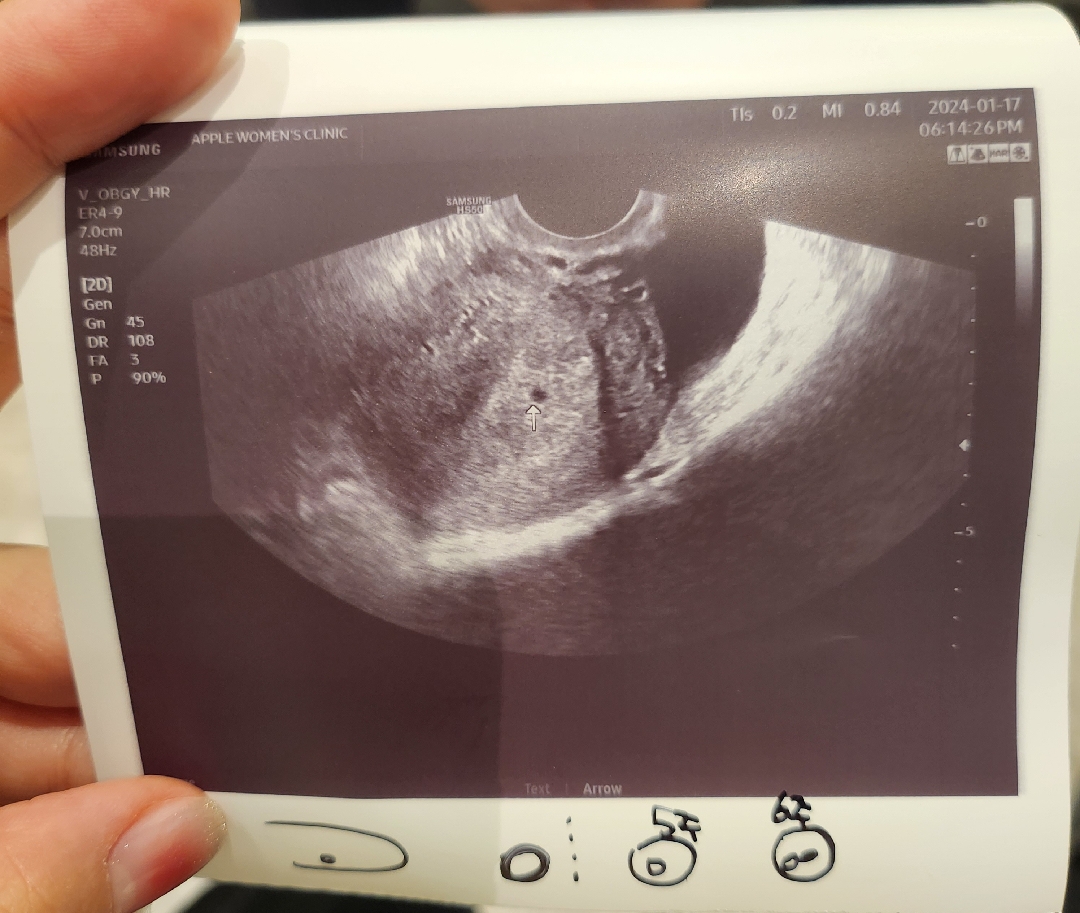

아기집이 작대요 ㅜㅜ

마지막 생리가 12월 6일이었고 빌리 주차계산으로 보면 6주 0일이라고 해서 기대하고 갔는데ㅜㅜ 피검사 수치는 9988이라 안정적이라고 하시는데 아기집이 너무 작아서 2주뒤에 다시오라고 하시네요 ㅜㅜ 지금 사진으로는 4주차쯤 인것 같다고 ... 저처럼 주차보다 아기집이 작은분도 계신가요? 초산이라 걱정이 되네요 ㅠㅠ 2주 못기다릴거같아요 흑..